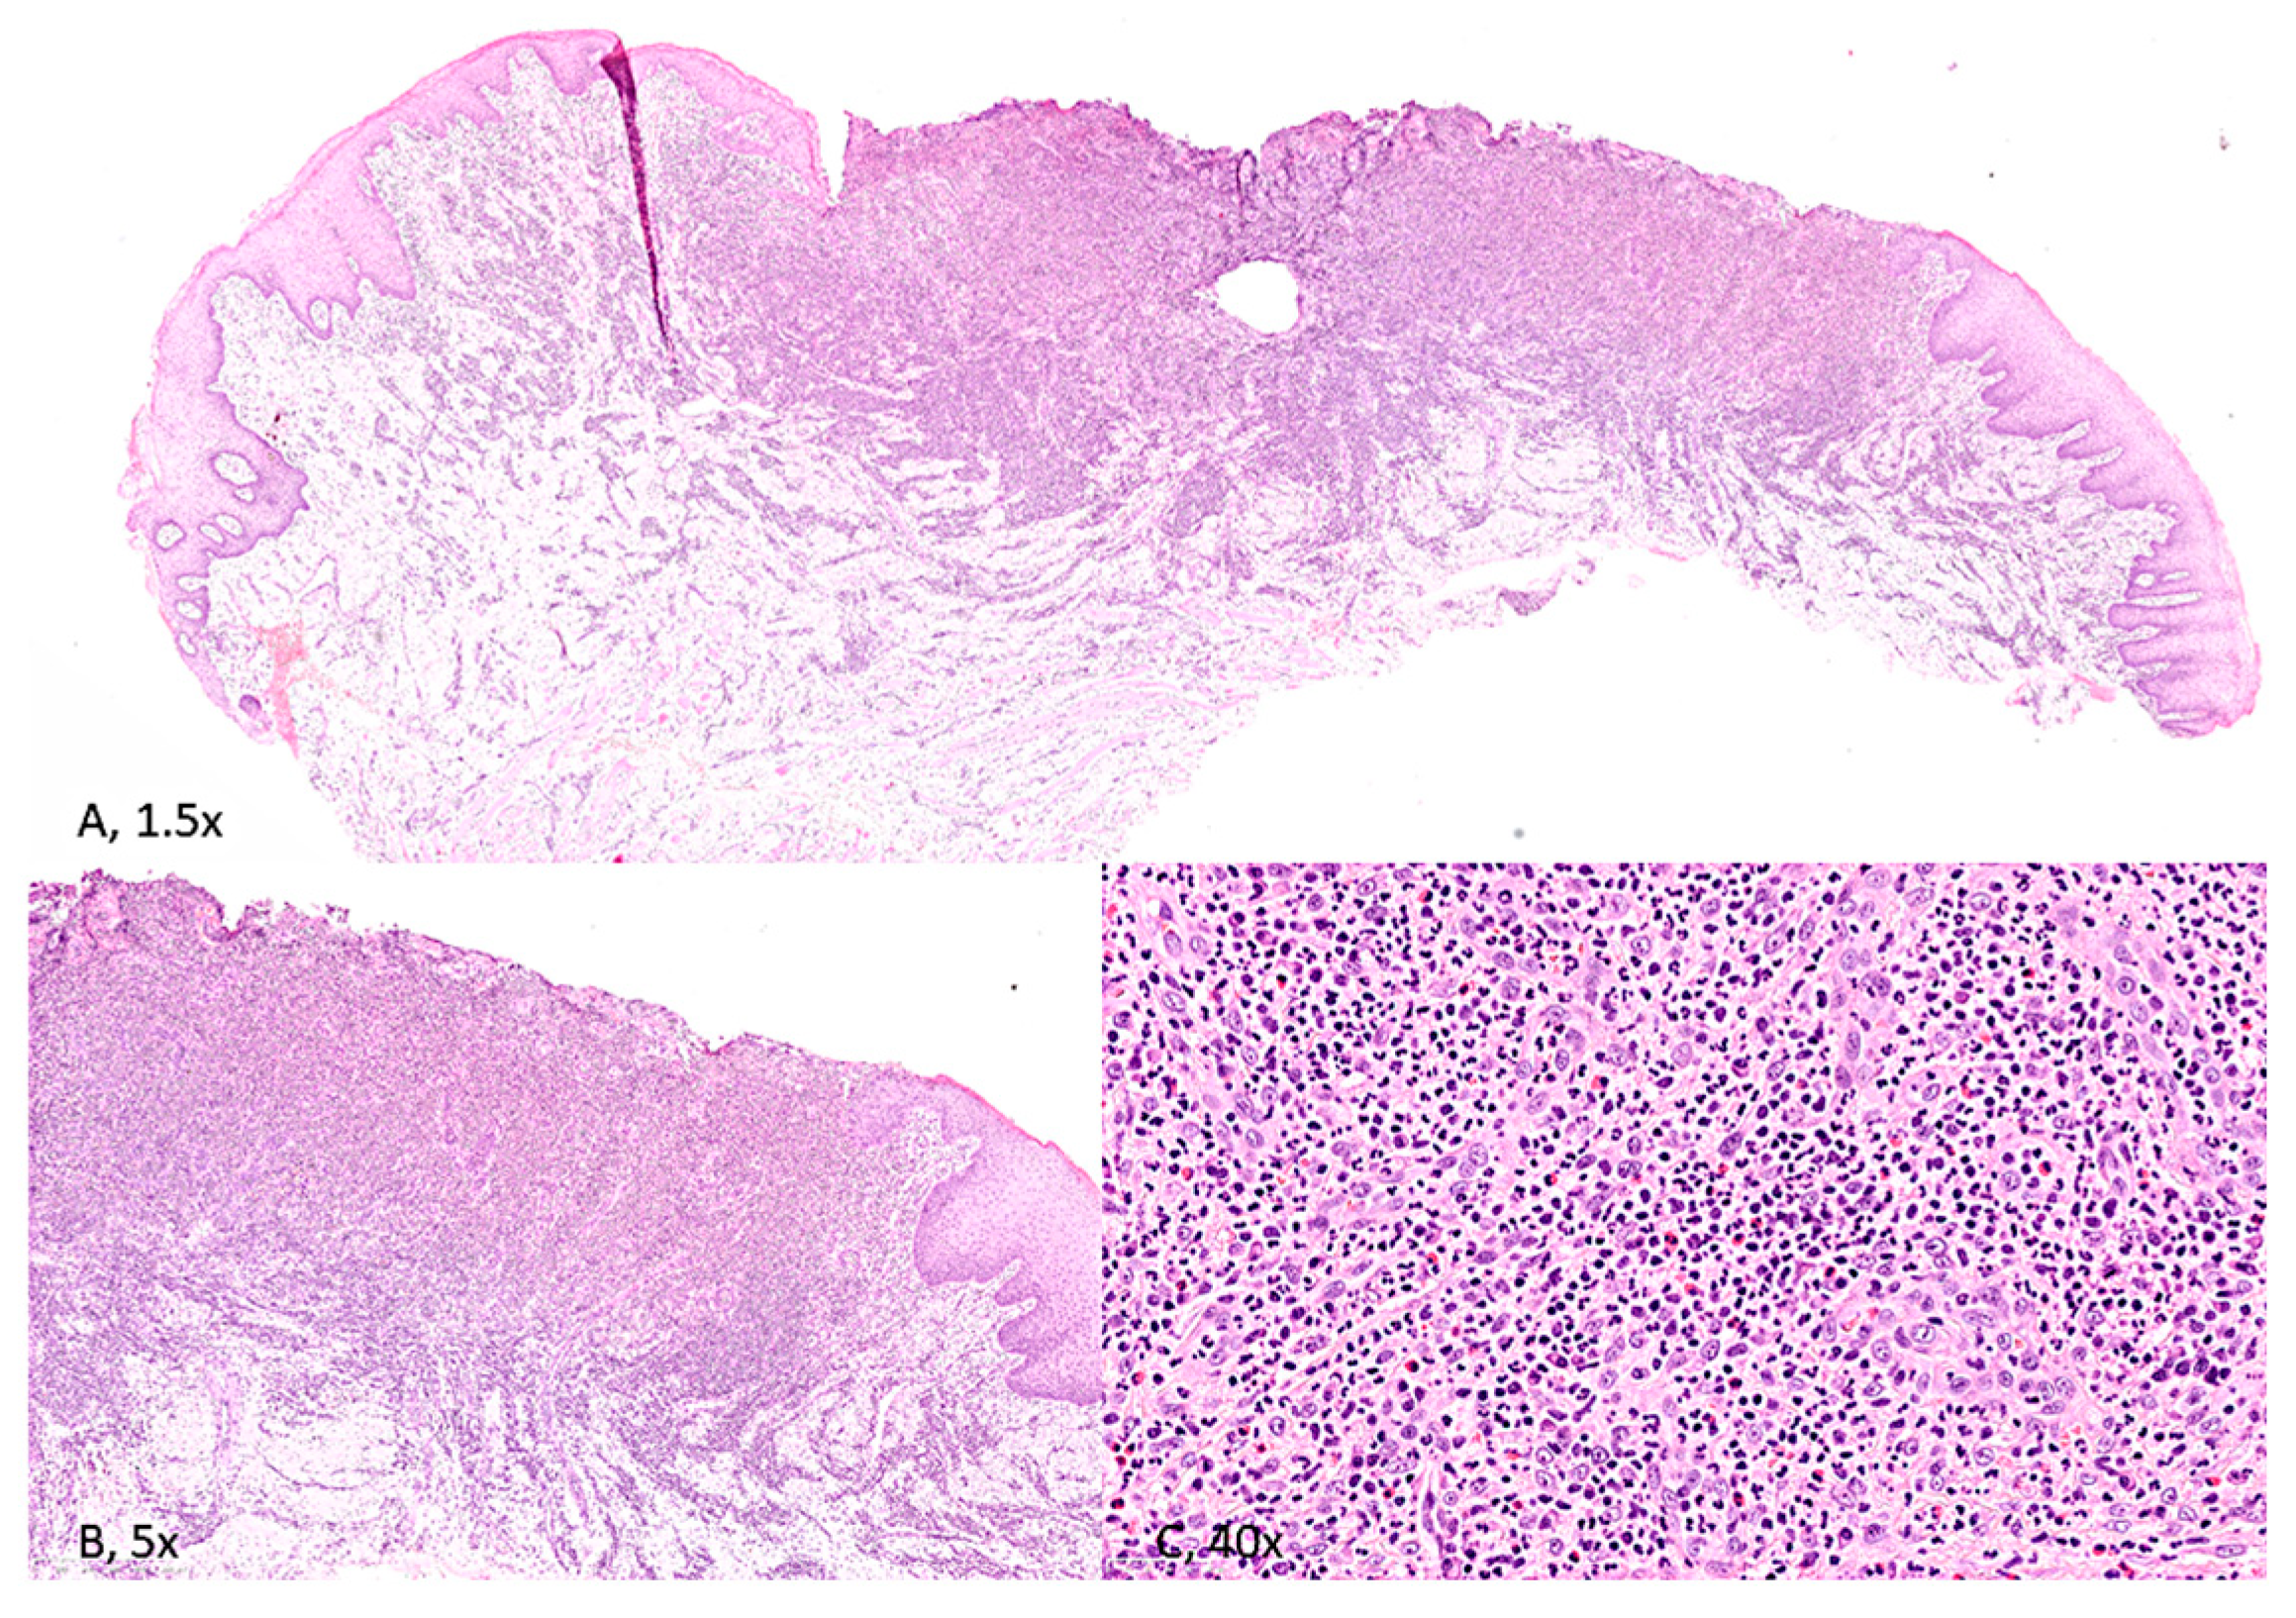

4.1. Histology and Immunohistochemistry